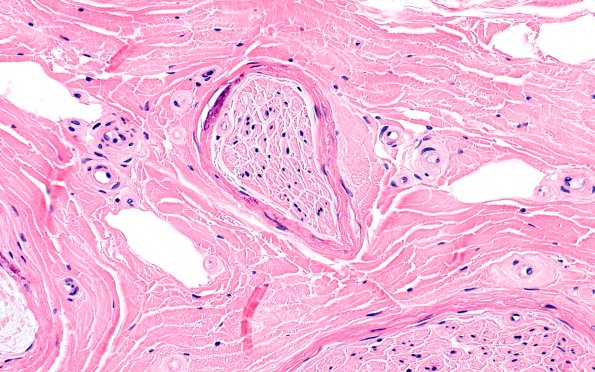

Washington University Experience | PERIPHERAL NEUROPATHY | 9B PERINEURITIS & PERINEURIAL PATHOLOGY | 6A4 (Case 6) H&E 40X 2

There are frequent prominent perineurial calcifications but no evidence of vasculitis or inflammation. ---- Not shown: One micron-thick, toluidine blue stained sections of the plastic embedded biopsy show fascicles with severe loss of large and small myelinated axons. There are rare structures suggestive of onion bulbs or pseudo-onion bulbs.